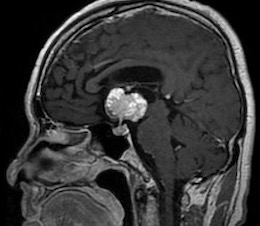

視力障害、記銘力障害で発症した頭蓋咽頭腫を両側前頭開頭、anterior interhemispheric approachで切除しました。トルコ鞍部や鞍上部にはほとんど局在しないためtranslamina-terminalis approachを選択しました。視床下部動脈を温存し、内減圧を繰り返し、焼き鳥テクニックとリングキュレットで狭い術野から腫瘍を起こして摘出しました。術後年齢が比較的若かったためかすぐに覚醒しました。